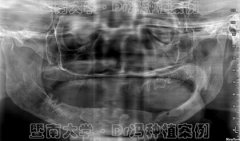

无牙颌也能种牙?穗华口腔医院穿颧种

穿颧种植技术一直被誉为是种植牙界珠穆朗玛峰式的顶级技术,也是很好的疑难...【详细】